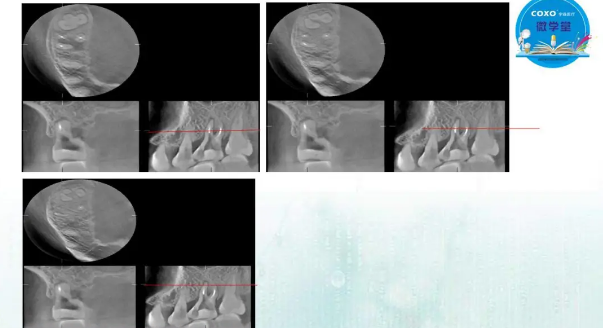

主講:孫書昱

主任醫(yī)師,牙體牙髓副主任, 廣東省口腔醫(yī)院牙體牙髓科 主任醫(yī)師。2003年碩士研究生畢業(yè),研究方向為牙體牙髓病學,擅長于牙體牙髓病的診斷、齲齒、牙髓炎、根尖周病的治療以及前牙美容修復。